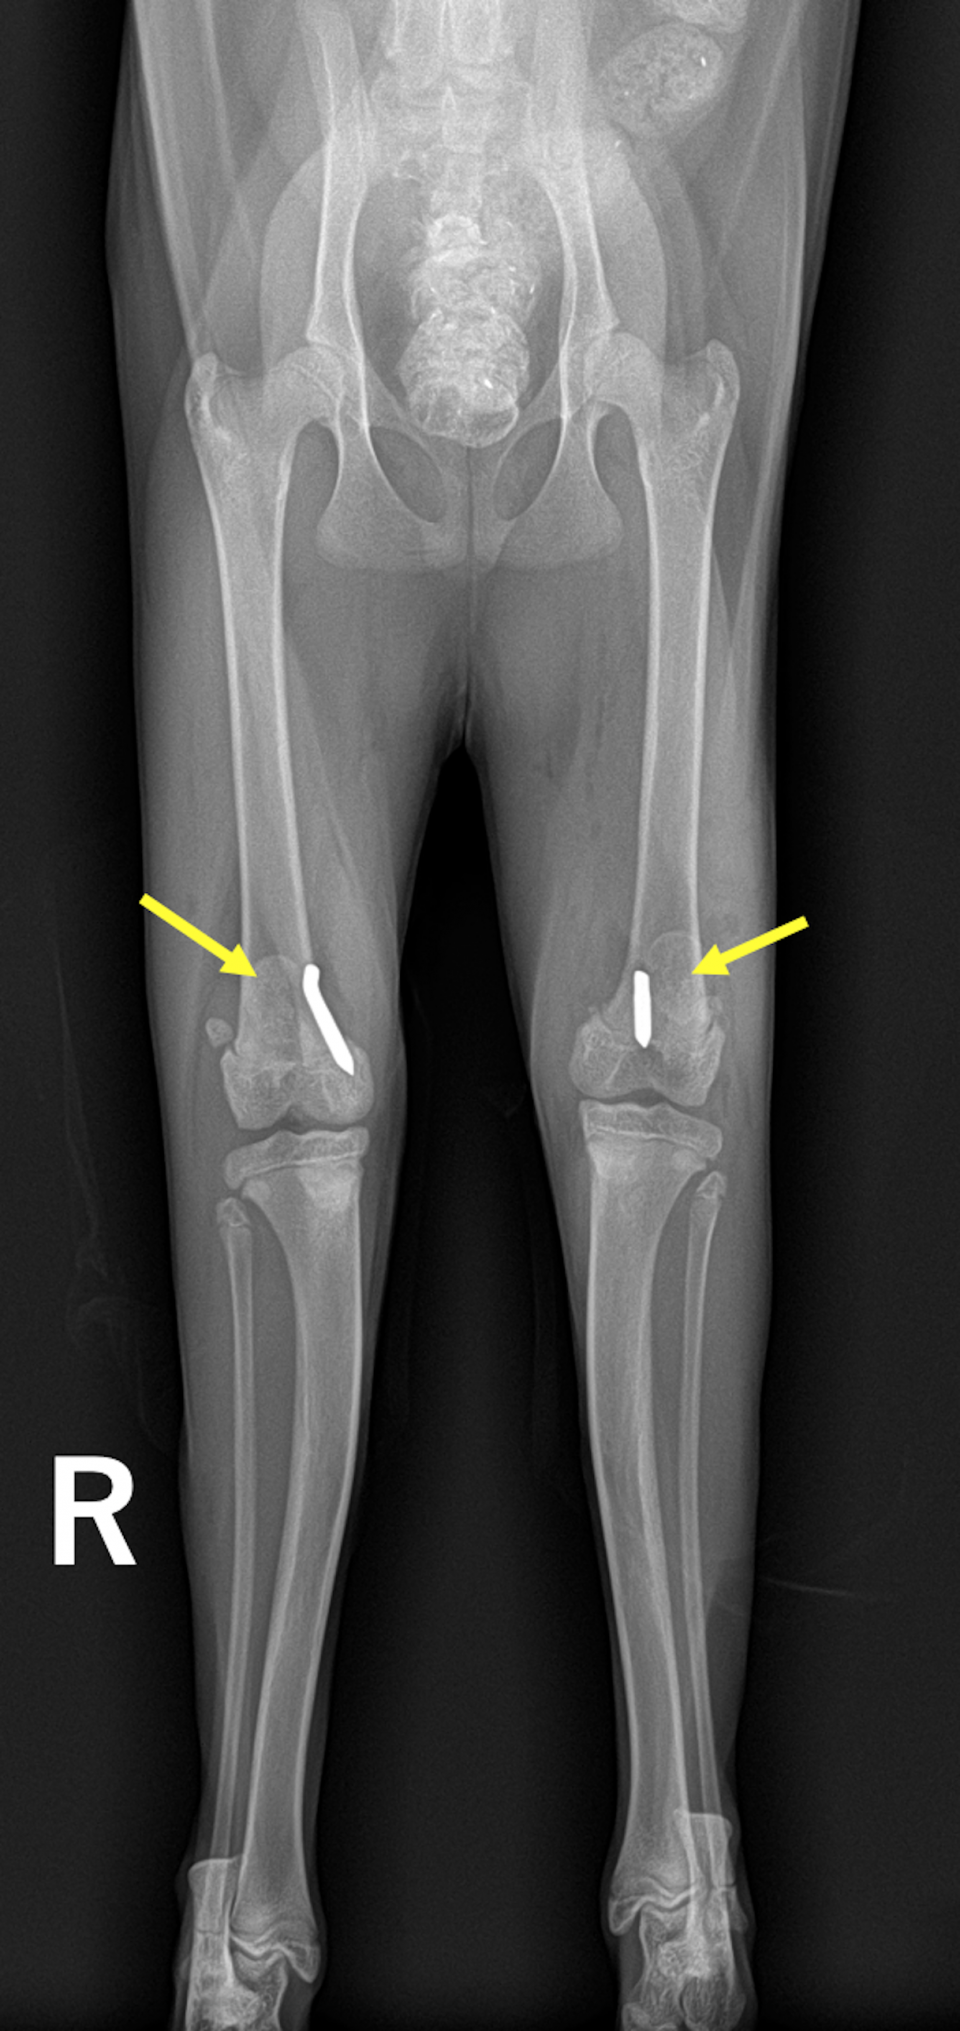

左右ともに滑車溝形成術、内側リリース、外側支帯縫縮術、脱臼防止ピンの設置を実施しました。

手術から1週間後の様子です。

左後肢の足の捻れが改善し、両後肢ともにしっかりとした負重が認められます。

Aちゃんは両側ともに重度の膝蓋骨内方脱臼があり、特に左側はグレード4で足の捻れが認められましたが、骨格変形は最小限でした。骨格変形が進行すると侵襲の強い術式や複数回の手術が必要になりますが、Aちゃんは早期治療ができたため脛骨粗面転位術や骨切り術などを行わずに良好に改善し、合併症もありませんでした。